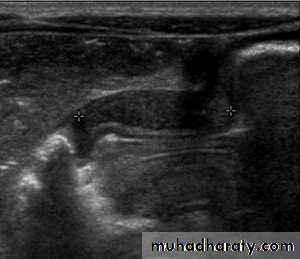

Hypertrophic pyloric stenosis refers to idiopathic thickening of gastric pyloric musculature which then results in progressive gastric outlet obstruction

In a normal situation, the pyloric muscle thickness (diame­ter of a single muscular wall on a transverse image) should normally be less than 3 mm (most accurate 3) and the length (longitudinal measurement) should not exceed 15 mm.